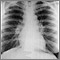

Often the disease is found in patients with visible physical signs who have an abnormal chest x-ray.

Different imaging tests may help diagnose sarcoidosis:

To diagnose this condition, a biopsy is needed. Biopsy of the lung using bronchoscopy is usually done. Biopsies of other body tissues may also be done.